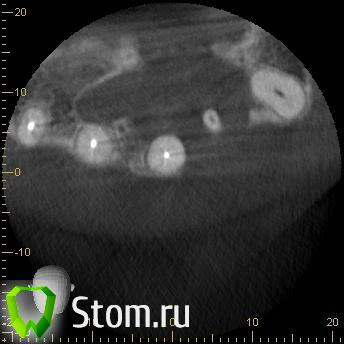

kriokov Опубликовано 20 марта, 2012 Поделиться Опубликовано 20 марта, 2012 Пац 60 лет, 13.03- диагносцирована нагноившаяся киста в\челюсти, вскрыт гнойник, антибактериальная и симптоматическая терапия. На КТ киста до 4 куб см ориентировочно, сквозной дефект с вестибулярной на небную поверхность, деструкция носонебного канала, деструктивный очаг небно за корнем 11. дно носа не критично. Имплантация в перспективе не планируется.Через 1 месяц планируется штатная цистэктомия с удалением 21 и 22. Коллеги, кто как небно мебрану выставляет? Дефект кости на небе 10 на 10 мм. Сам думаю, что под полнослойный лоскут на небе придется устанавливать, попробую отслоиться со стороны костной раны. Ссылка на комментарий

wladdX Опубликовано 22 января, 2014 Поделиться Опубликовано 22 января, 2014 (изменено) Пациентка 33-х лет, обратилась с жалобами на болезненную припухлость на тв. нёбе. При обследовании выявлена киста резцового канала, самопроизвольно вскрывшаяся.Через перф.отверстие отмыта, воспаление стихло, свищевого хода не сформировалось (перф.отверстие эпителизировалось). Встаёт вопрос об операции. Планируется нёбный доступ. Как думаете, коллеги? Изменено 22 января, 2014 пользователем wladdX Ссылка на комментарий